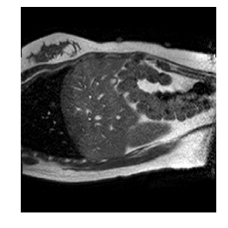

With this motivation, [6] proposed a convolutional neural network (CNN) based approach for temporal interpolation of navigators. Their CNN takes as inputs a fixed number of acquired images and learns to predict the missing images directly in the intensity space. This approach, which we call the Simple Convolutional Interpolation Network (SCIN), is a ’black-box’ formulation that does not incorporate any prior information about the interpolation process. Image prediction is guided only by the cost function used to optimize the network parameters. The issue with this is that it is unclear whether the image similarity measures that are generally used as cost functions suffice to ensure fidelity of the generated images to the original images. Indeed, Fig. 1b shows a case where an image interpolated using SCIN is quite blurry and misses several liver and lung structures present in the original image.

(a) (b) (c)

Qualitative results are shown in Fig. 4. We observe no large qualitative differences in the performances of MFIN and MFINc for either loss function. Since, MFINc-SSIM provides the best quantitative results, we show interpolated images from this method and compare them against SCIN-SSIM. Both methods perform well when the motion between the neighbouring images is low. This is reflected in the absence of any structures in the error images in Fig. 4.1. However, RMSE is lower for SCIN because it produces a denoised interpolated image, while MFIN carries over the noise pattern from the neighbouring known image. Whenever there exists high motion between the images being interpolated, SCIN produces blurry images and often misses image structures. This can be observed in cases 2-4 in Fig. 4. For all these cases, MFINc (and also MFIN) produces sharp images and largely preserves structures in the images. Fig. 4.2 shows a case where MFINc additionally has a much better performance with respect to image alignment. Fig. 4.3 shows a representative case, with small improvement in image alignment, yet worse RMSE and SSIM values for MFINc. Finally, Fig. 4.4 shows a case, where MFINc produces worse alignment of structures than SCIN.